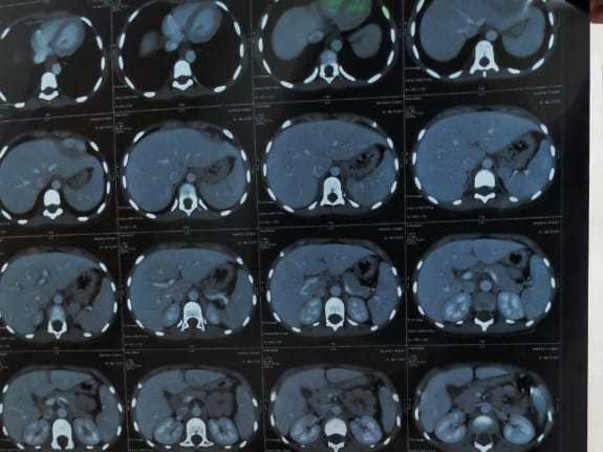

My name is Bhargavi my age is 8yrs .. I fell down playing with my fellow friends one day. Our parents took me to the hospital .. where the doctor tested me and said there was a blood clot in the brain ... keep me alive నేను .. I have to study well. I have to play with my parents .. keep me alive